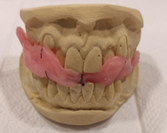

Plan de tratamiento: Debido a todo lo expuesto se decidió colocar un aparato de avance mandibular tipo monoblock para recapturar el disco. Para ello se inició con la realización de una mordida constructiva para la confección del aparato, se llevó a una coincidencia de las líneas media y un adelantamiento mandibular de 3 mm (Figuras D, E y F). Posteriormente se envió los registros para la confección del dispositivo de avance mandibular tipo monoblock (Klammt Clase II) que fue instalado en marzo del 2023 constatando de que se encuentre totalmente adaptado (G), las indicaciones de uso fueron más de 20 horas al día aconsejando que la paciente se lo retire únicamente para comer y para el aseo respectivo. Los controles se realizaron a las 2 semanas y después con una frecuencia mensual durante 12 meses.